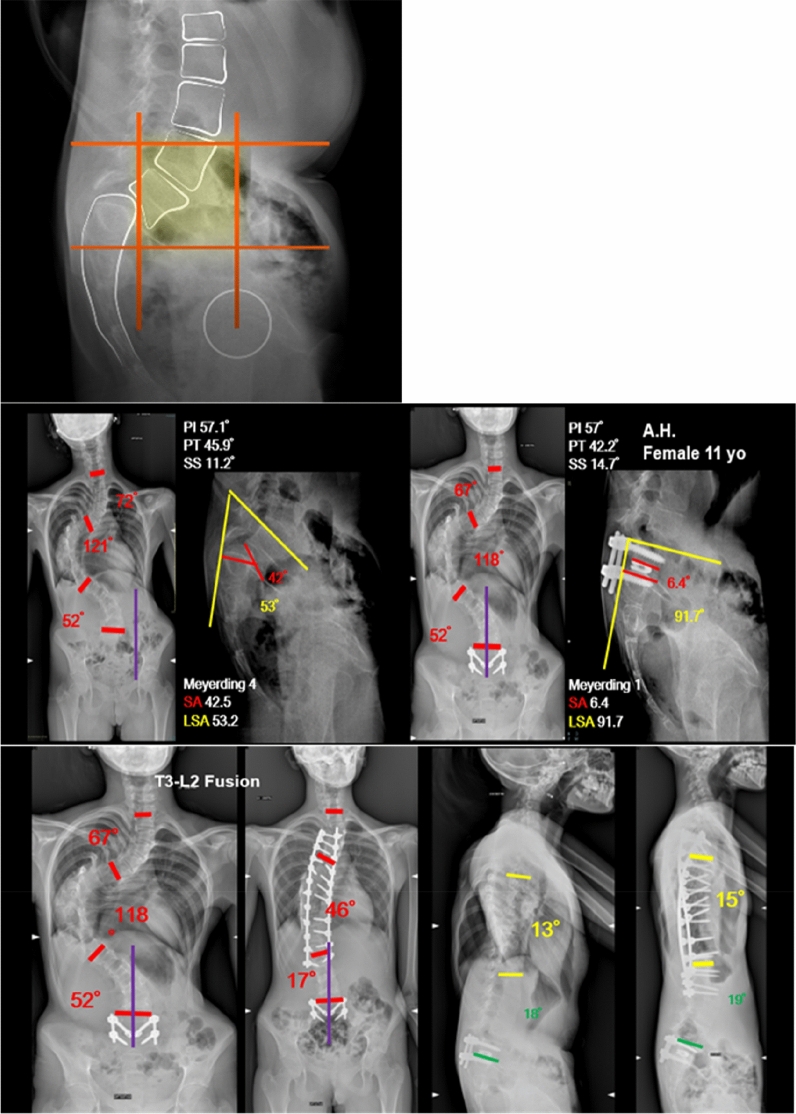

When an associated thoracic scoliosis requiring future surgical treatment was present (2 cases), L4 was not included in the fusion area even if it laid in the unstable zone, in order to spare motion segments (Fig. 3).

Fig. 3.

A case of spondylolisthesis associated with adolescent idiopathic scoliosis